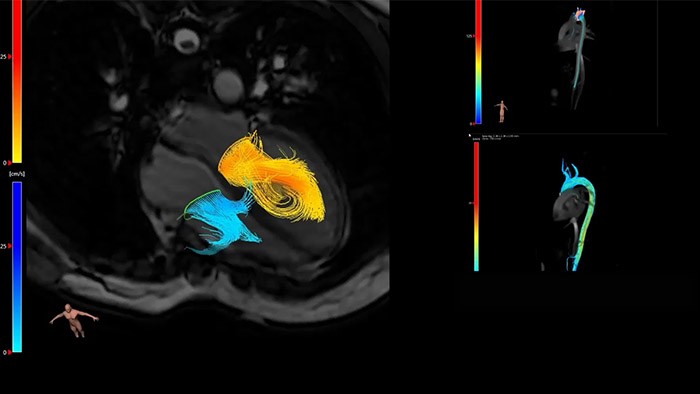

Visualize and evaluate blood flow

Visualise and evaluate blood flow

IntelliSpace Portal MR Caas5,6 4D Flow post-processing solution enables generation of 3D volume reconstructions, to visualise and evaluate blood flow in cardiovascular structures, including heart valves, chambers, and vessels, based on cardiovascular MR 4D Flow imaging.